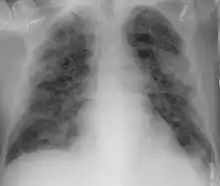

Imaging

Chest CT scans may be helpful to diagnose COVID‑19 in individuals with a high clinical suspicion of infection but are not recommended for routine screening.[163][175] Bilateral multilobar ground-glass opacities with a peripheral, asymmetric, and posterior distribution are common in early infection.[163][176] Subpleural dominance, crazy paving (lobular septal thickening with variable alveolar filling), and consolidation may appear as the disease progresses.[163][177] Characteristic imaging features on chest radiographs and computed tomography (CT) of people who are symptomatic include asymmetric peripheral ground-glass opacities without pleural effusions.[178]

Many groups have created COVID‑19 datasets that include imagery such as the Italian Radiological Society which has compiled an international online database of imaging findings for confirmed cases.[179] Due to overlap with other infections such as adenovirus, imaging without confirmation by rRT-PCR is of limited specificity in identifying COVID‑19.[178] A large study in China compared chest CT results to PCR and demonstrated that though imaging is less specific for the infection, it is faster and more sensitive.[162]